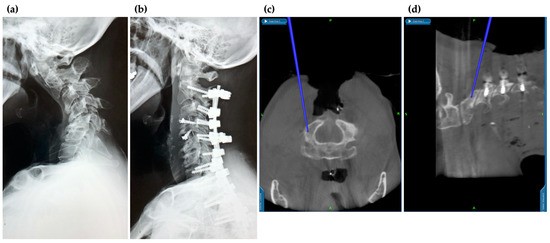

3.3. Application of Navigation Systems in Cervical Spine Surgery

3.6. Robotics-Assisted Surgery